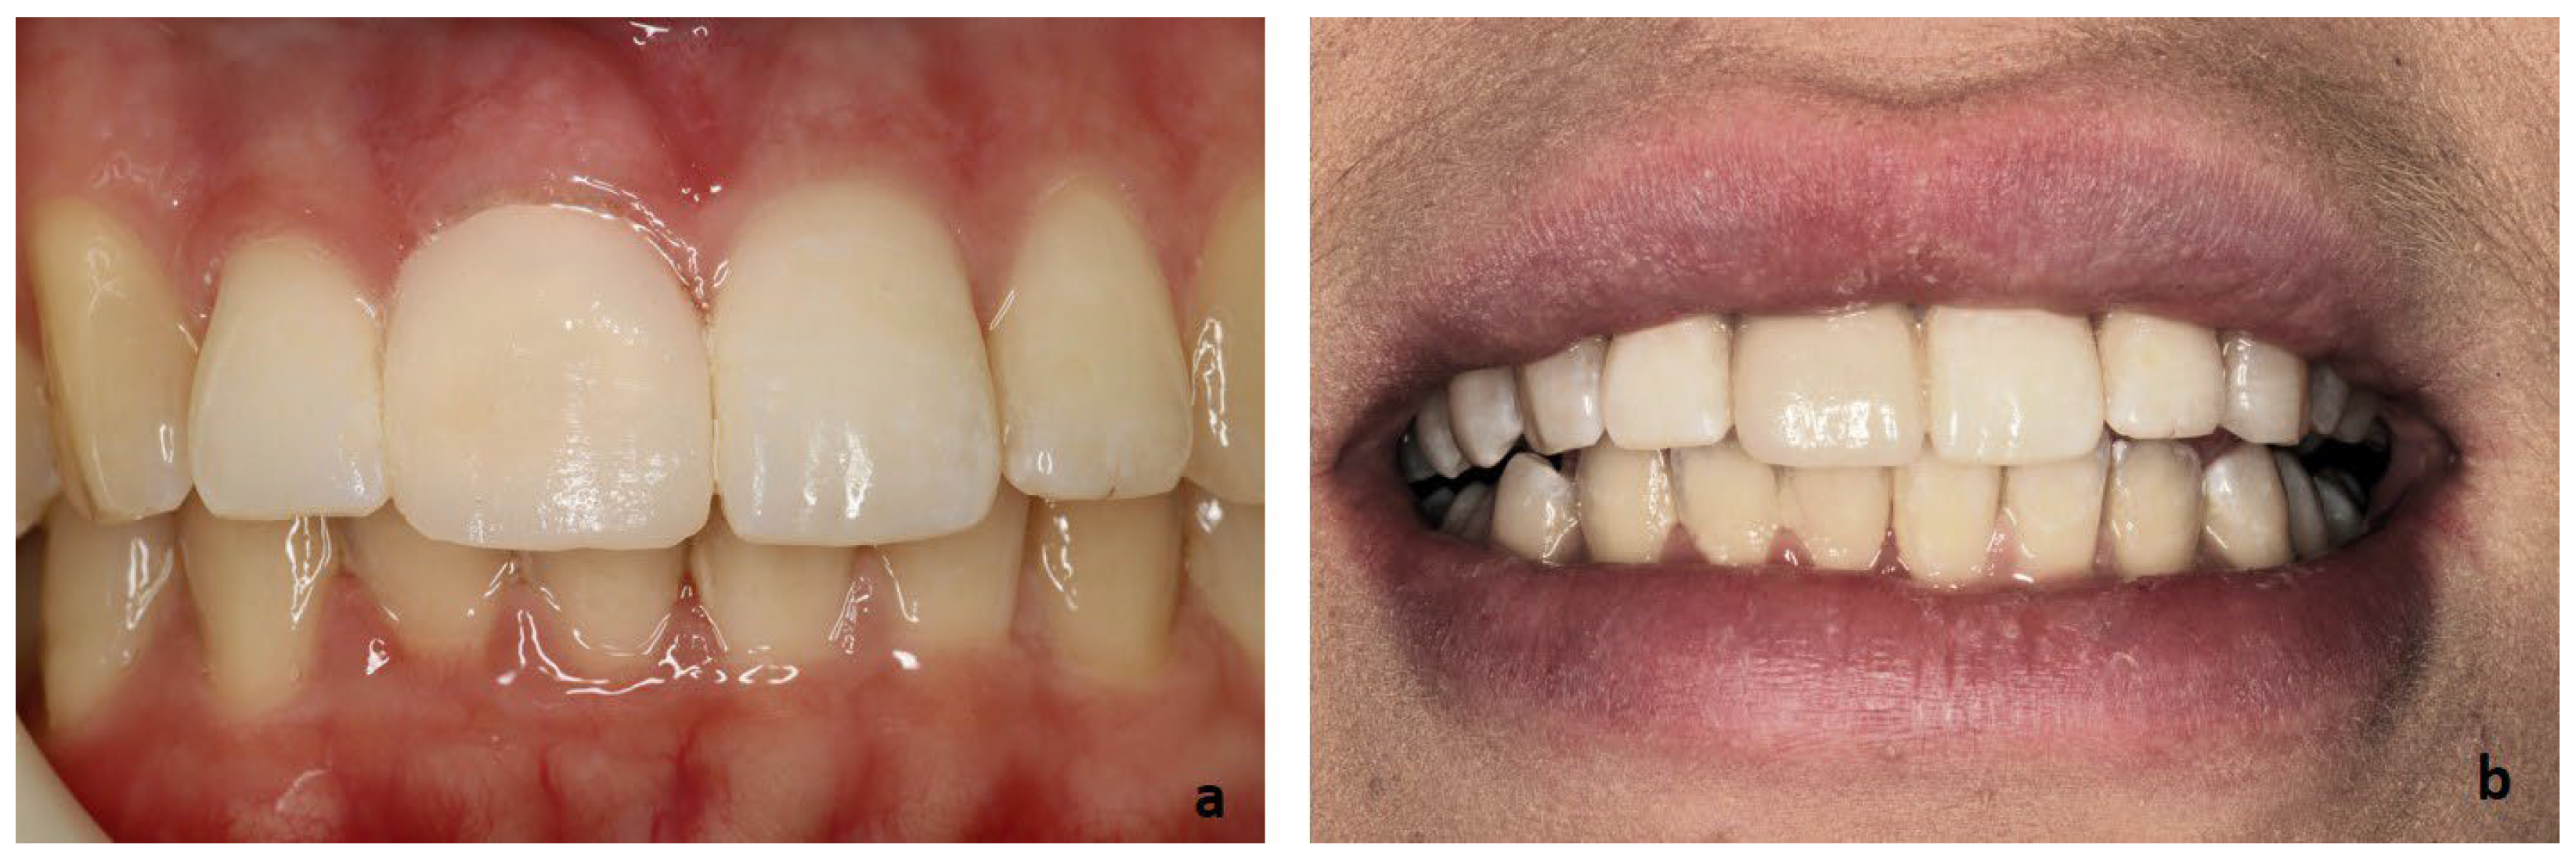

2. Clinical Case